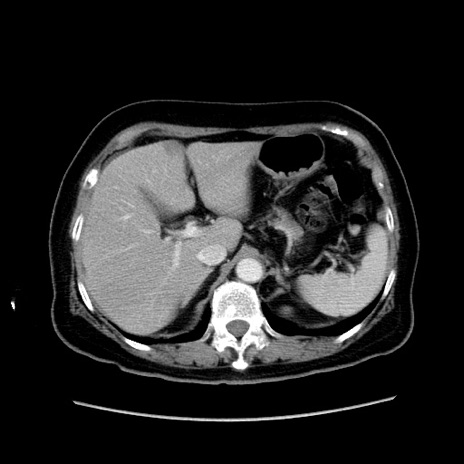

症例19(横断像)

【症例】80歳代女性

【主訴】下腹部痛

【現病歴】約8時間前より下腹部痛の出現あり、救急外来受診。

【既往歴】両側付属器切除

【身体所見】意識清明、下腹部正中に手術痕あり、その部位に一致して圧痛と反跳痛あり。腸蠕動音は亢進。

【データ】WBC 9300、CRP 0.15